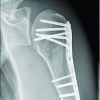

Comparison with published data highlights that the majority of BASD cases entail associated fractures, especially of the greater tuberosity, and may require surgical stabilization [4,5,6,7]. Our patient being an exception with pure dislocation and no fracture, reinforcing that closed reduction remains standard for such uncomplicated presentations [1,2,9]. Moreover, this case reiterates that seizure-related BASD likely results from secondary trauma at the time of convulsive collapse, with the characteristic forced position of abduction and external rotation precipitating anterior displacement, contrasting the classic mechanism of internal rotation-induced posterior dislocation typically seen in seizures [3,4,5,6].

Closed reduction under adequate analgesia is the standard of care in acute, uncomplicated cases. Immobilization for 2–3 weeks, followed by structured physiotherapy, ensures shoulder stability and mobility. Surgical stabilization may be necessary in cases with associated fractures, rotator cuff injuries, or recurrent dislocations.